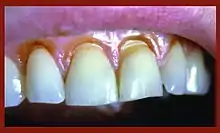

Tooth tissue is gradually weakened causing tissue loss through fracture and chipping or successively worn away leaving a non-carious lesion on the tooth surface. These lesions occur in both the dentine and enamel of the tooth. These lesions generally occur around the cervical areas of the dentition.[6]

Abfraction lesions will generally occur in the region on the tooth where the greatest tensile stress is located. In statements such as these there is no comment on whether the lesions occur above or below the CEJ. One theory suggests that the abfraction lesions will only form above the CEJ.[7][8][9][10] However, it is assumed that the abfraction lesions will occur anywhere in the cervical areas of affected teeth. It is important to note that studies supporting this configuration of abfraction lesions also state that when there is more than one abnormally large tensile stress on a tooth two or more abfraction lesions can result on the one surface.[4]

When looking at abfraction lesions there are generally three shapes in which they appear, appearing as either wedge, saucer or mixed patterns.[7] Wedge and saucer shaped lesions are the most common, whereas mixed lesions are less frequently identified in the oral cavity.[7] In reference to figure 1, wedge shaped lesions have the sharpest internal line angles and saucer/mixed shaped lesions are either smooth internally, or a variety.